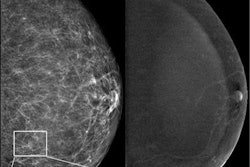

60-year-old woman with cirrhosis and portal hypertension who underwent contrast-enhanced CT as pre-liver transplant evaluation. Patient weight was 164 lbs. Automated deep-learning artificial intelligence tool was used to segment spleen and thereby compute splenic volume. Axial image shows spleen segmentation (orange overlay). Automated splenic volume was 1,097 ml, above weight-based splenic volume threshold for determining splenomegaly of 350 ml. True-craniocaudal splenic length was 15.5 cm, and maximum-3D splenic length 18.7 cm. These length measurements would indicate presence of splenomegaly at all thresholds used. Image and caption courtesy of the American Journal of Roentgenology.The team reported that the AI algorithm effectively calculated splenic volumes from CT exams in 8,853 patients from the primary cohort of 8,901 (99%), and that splenic volume had a statistically significant association with patient weight.